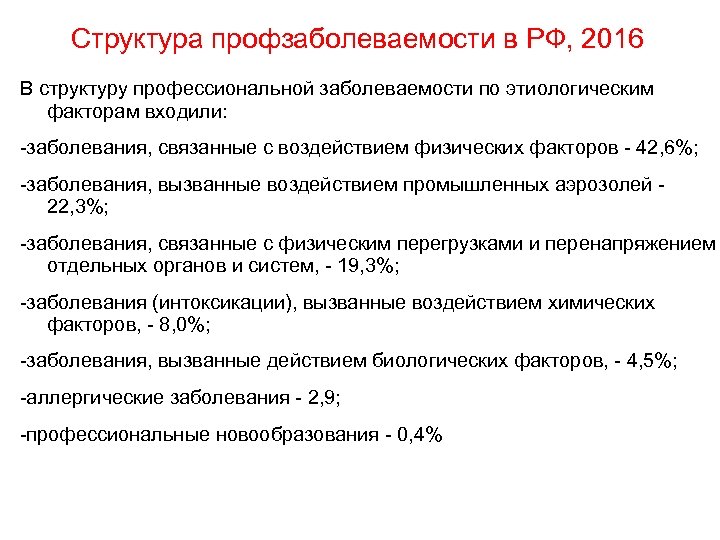

Структура профзаболеваемости в РФ, 2016 В структуру профессиональной заболеваемости по этиологическим факторам входили: заболевания, связанные с воздействием физических факторов 42, 6%; заболевания, вызванные воздействием промышленных аэрозолей 22, 3%; заболевания, связанные с физическим перегрузками и перенапряжением отдельных органов и систем, 19, 3%; заболевания (интоксикации), вызванные воздействием химических факторов, 8, 0%; заболевания, вызванные действием биологических факторов, 4, 5%; аллергические заболевания 2, 9; профессиональные новообразования 0, 4%

Структура профзаболеваемости в РФ, 2016 В структуру профессиональной заболеваемости по этиологическим факторам входили: заболевания, связанные с воздействием физических факторов 42, 6%; заболевания, вызванные воздействием промышленных аэрозолей 22, 3%; заболевания, связанные с физическим перегрузками и перенапряжением отдельных органов и систем, 19, 3%; заболевания (интоксикации), вызванные воздействием химических факторов, 8, 0%; заболевания, вызванные действием биологических факторов, 4, 5%; аллергические заболевания 2, 9; профессиональные новообразования 0, 4%